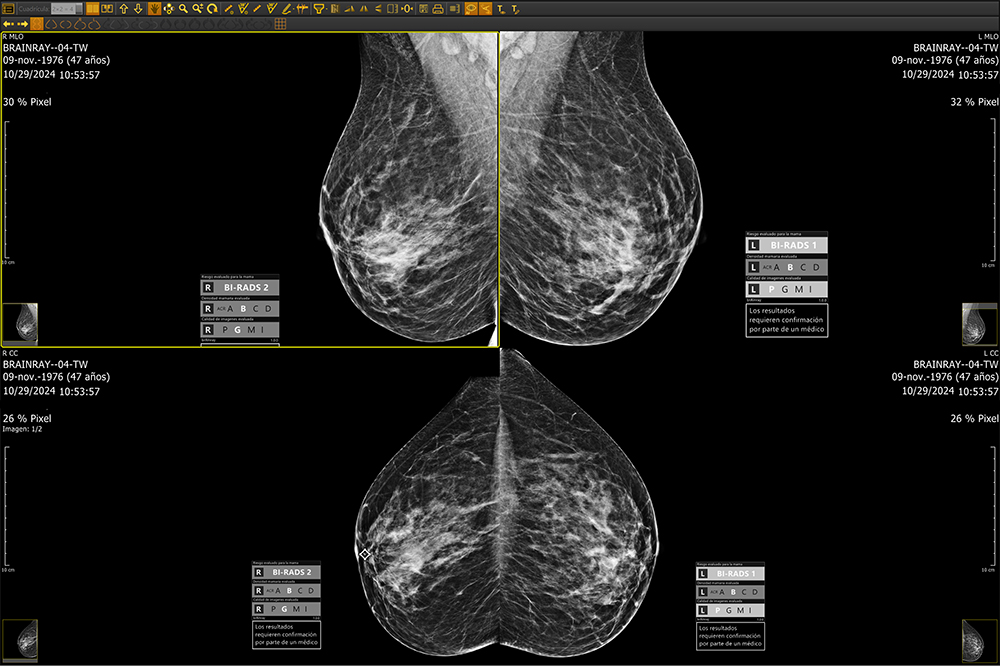

Whether deployed on-site or via the cloud, brAInray® seamlessly integrating with any PACS system, brAInray® analyzes full-field digital mammograms (FFDM) to detect and mark suspicious regions—highlighting calcifications, masses, asymmetries, and architectural distortions. It categorizes findings using ACR BI-RADS® standards and delivers automatic structured DICOM reports for clear, consistent clinical insights.